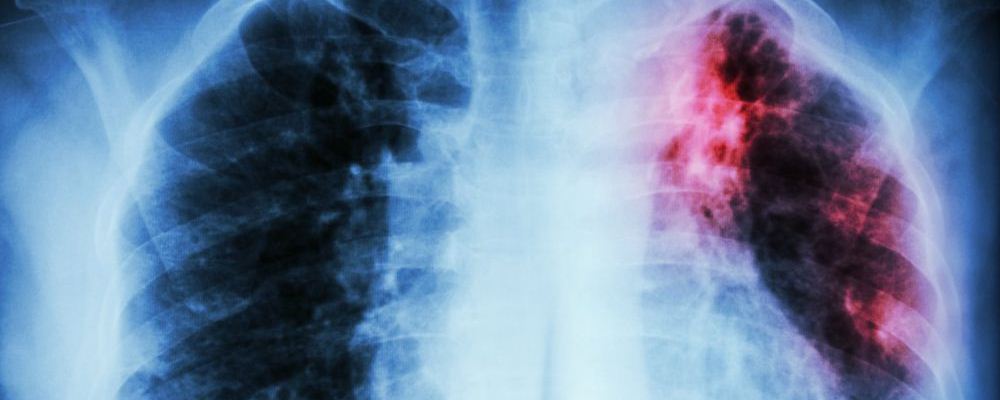

12歲男孩肺癌晚期 日常要重視養(yǎng)肺措施

肺癌可是很可怕的疾病,其發(fā)病率和死亡率都很高,是一種威脅人的健康和生命的惡性腫瘤。早期發(fā)現(xiàn)問題治療恢復(fù)的可能性比較大,可是到了肺癌晚期的時候,就算就回來了也沒幾年好活了。可是,最近湖南有個家庭發(fā)生了一件糟心的事情——12男孩患上原發(fā)性支氣管肺癌晚期疾病。這實在是令人震驚,這么小的年紀(jì)就得了這種病。

近日,湖南邵陽一名12歲男孩因鎖骨處長包塊,到醫(yī)院檢查,竟然得了原發(fā)性支氣管肺癌晚期!這種癌癥患病率和死亡率位居全球第一,但在未成年人中比較罕見。而造成此種疾病的原因,竟然是“懶,經(jīng)常熬夜,早餐基本上不吃!”